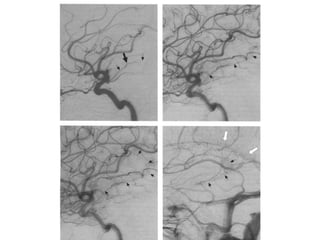

As setas indicam M2 contornando o

sulco circular da ínsula. A seta maior o

ponto silviano posterior, emergência da

artéria angular.

As setas indicamM2 contornando o sulco circular da ínsula. A seta maior o ponto silviano posterior, emergência da artéria angular.